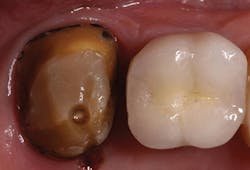

A 55-year-old female presented to my office for an evaluation of a crown placed on tooth No. 15 within the last few years. Her complaints included: "It feels big. I get a ton of food trapped in it, and it is kind of ugly." A bitewing was taken (Fig. 1) revealing an ill-fitting crown on No. 15. An intraoral photo was also taken (Fig. 2) confirming an oversized PFM with poor contours. The decision was made to remove and replace the crown.

FIG. 2